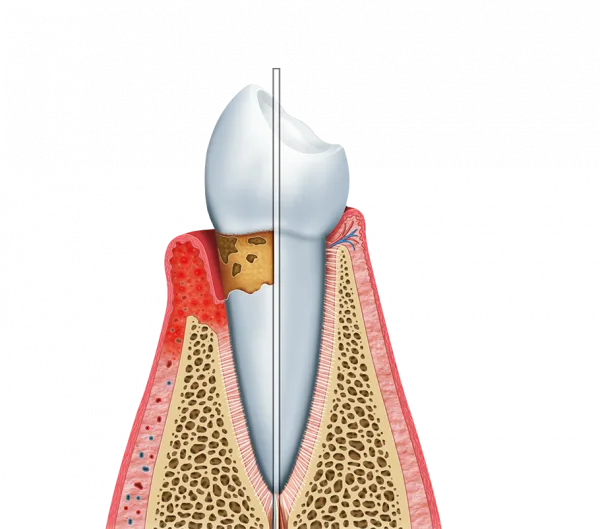

Este profissional, focado na saúde dos tecidos moles, é treinado para reverter quadros inflamatórios antes que eles evoluam para problemas irreversíveis, como a periodontite.

Através de um olhar clínico apurado, o especialista identifica sinais sutis de sangramento e inchaço, fundamentando um plano de ação preventivo que protege os dentes naturais e preserva a sustentação óssea da arcada no cotidiano.

Ao buscar um suporte qualificado, o cliente cuida para que a inflamação seja tratada na raiz, estabelecendo um ambiente bucal equilibrado e prevenindo que bactérias nocivas migrem para a corrente sanguínea, protegendo sua saúde de forma integral.

Diagnóstico Precoce: Identificação imediata de patologias gengivais em estágio inicial;

Estética Gengival: Tratamentos que reduzem o aspecto avermelhado e inchado das gengivas;

Preservação Dental: Controle rigoroso para evitar a retração gengival e a perda de dentes.